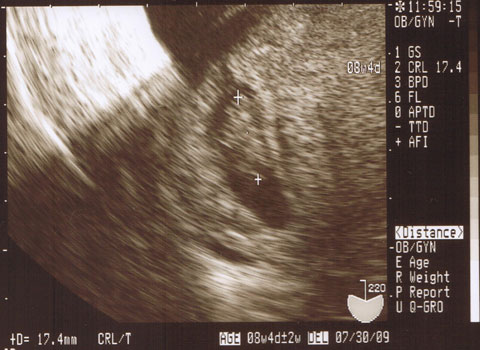

3週間ぶりにお豆に会いました。

パパも一緒に豆ちゃんを見たよ。

小っちゃい小っちゃい心臓が元気に動いてました。

8w4dの大きさだったらしいです。

4日分でかいんですって!!うちの豆!!

初めてパパと豆と3人家族なんだ〜って思いました。

母子手帳もらいました。

お豆はちゃんと8月に生まれてきてください。

あまり早く生まれないでね。